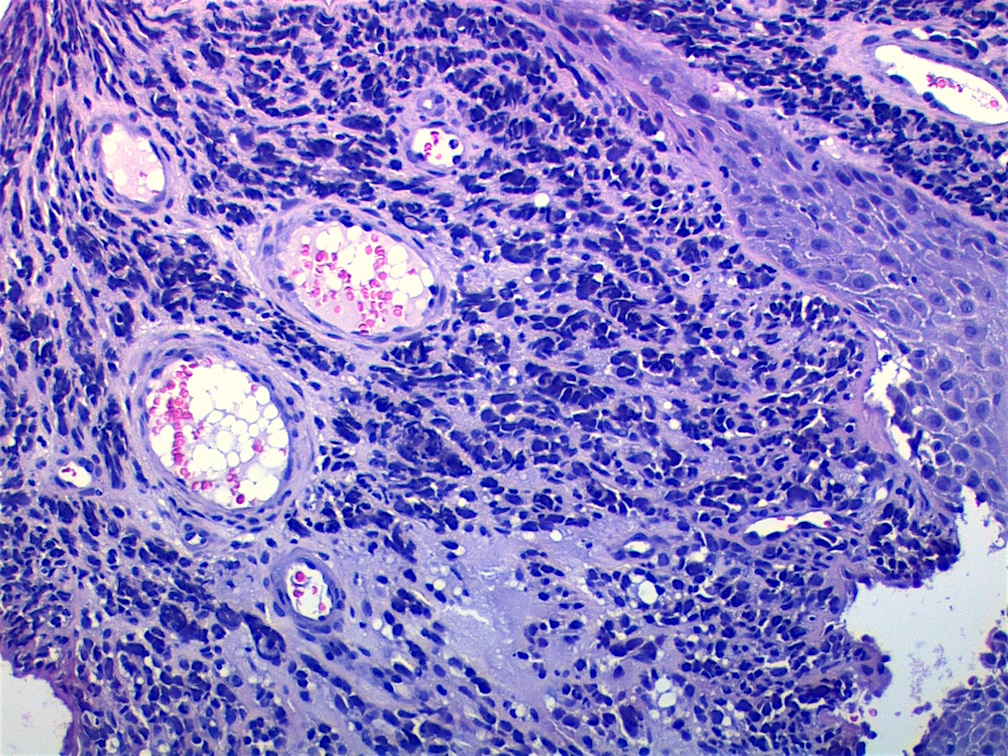

- Composed of primitive mesenchymal cells that show variable degrees of skeletal muscle differentiation

- They are moderately cellular but in the typical pattern often contain both hypocellularity and hypercellular areas with a loose, myxoid stroma

- Perivascular condensations of tumor cells in the less cellular regions are common

- Sheets of small, stellate, spindled or round cells with scant or deeply eosinophilic cytoplasm and eccentric, small oval nuclei with a light chromatin pattern and inconspicuous nucleoli

- Can occasionally identify tumor cells that contain generous amounts of eosinophilic cytoplasm, a feature of rhabdomyoblastic differentiation (so called strap cells)

Microscopic (histologic) images

Contributed by Erdener Özer, M.D., Ph.D. and Mark R. Wick, M.D.

Contributed by Carolina Martinez Ciarpaglini, M.D., Ph.D. (Case #276) - tonsillar mass